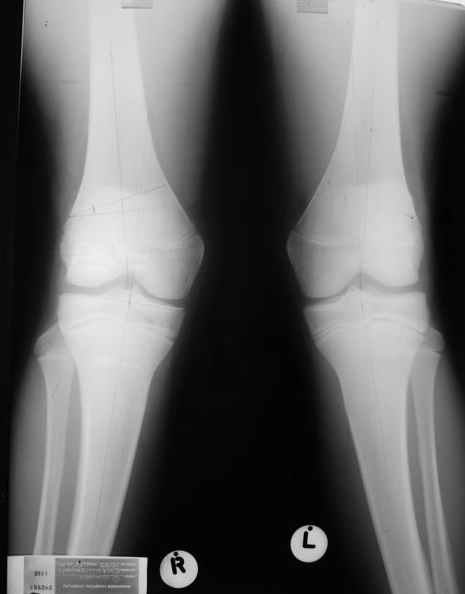

Уважаемый Евгений ! Спасибо за ответ, но мне представляется, что в нашем случае основной проблемой является не столько прогрессирующий вальгус конечности, сколько несросшийся перелом мыщелка бедра и дефект мыщелка большеберцой кости - вероятно первичная репозиция выполнялась без пластики.

Относительно "рубцовой подушки" я имел в виду остатки мениска ( частично вколоченного в дефект мыщелка и фрагменты хряща), все таки на рентгенограммах суставная щель в этом отделе чем то заполнена. Что касается некроза мыщелка бедра, то мне кажется он уже наступил - томограмма ноябрь5.

С учетом всего сказанного - наличия прогессирующего вальгуса конечности, довольно приличного объема движений, имеющегося, вероятно, некроза мыщелка бедра, наиболее рациональным представляется удалить пластину с б\б кости, произвести остеотомию б\б кости с коррекцией вальгуса, разгрузив тем самым наружный отдел сустава, и синтезировать фрагменты голени накостным фиксатором. Максимально тано начать восстановление движений в суставе. Скорее всего рано или поздно речь о протезировании всеже возникнет, но мы хотя бы будем иметь приличную ось конечности.

С *вколоченным* мениском встречаться не приходилось, нередко при импрессионных переломах наблюдал центральную дислокацию мениска по типу bucket handle, что в этой ситуации может объяснить сгибание сустава до 90 и разгибание 160 градусов, отчасти невозможность полностью разогнуть ногу при Рг графии сустава затрудняет интерпретацию прямой проекции сустава.

Тут ситуация совсем другая. Деформация не около-, а самая что ни на есть внутрисуставная. Покорректировать внешний вид конечности путем остеотомии дистального отдела бедра и high tibia (плюс или минус клин, одномоментно-постепенно, аппарат-пластина-стержень - дело третье) не сильно сложно, но это не решение проблемы. У больной, по

сути отсуствует латеральный отдел коленного сустава, что требует костно-пластических вмешательств непосредственно на артикулирующих

поверхностях.

Может быть, целесообразней сразу протез, чем тот же протез, но после сложных, но сомнительно результативных операций типа замещения алломыщелком, моделирующих резекций и т.п.? Ну и в любом случае движения лучше бы разработать получше до любой операции.